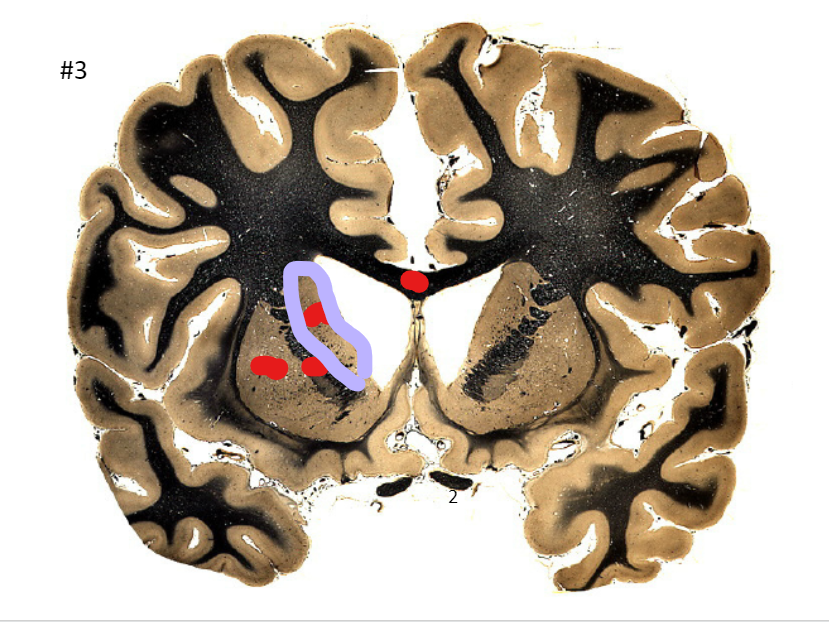

what is the circled area (#3)?

A

the corpus callosum

Q

the caudate nucleus

7

the internal capsule

8

the putamen

9

the optic nerve